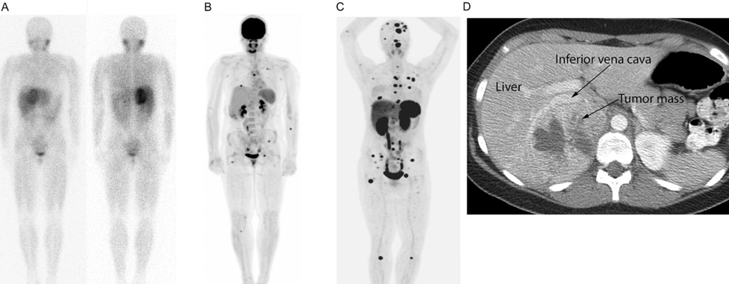

MIBG therapy (also known as 131I-MIBG therapy) is a form of radionuclide therapy currently being used in patients with a few types of cancer.

A small quantity of MIBG (meta-iodobenzylguanidine) molecule attached to radioactive iodine-131 is injected intravenously into the patient. The MIBG molecule targets the radiation of Iodine-131 (131I) to the cancer target sites. The delivered radiation then kills the cancer cells.